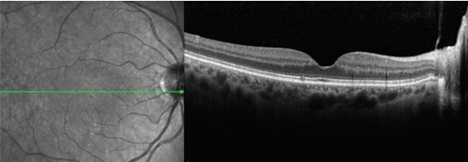

Retinal OCT allows us to assess the layers that make up the retina and looks like this: